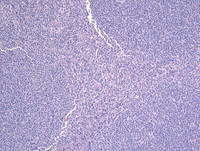

Figure 3: H&E in Follicular Lymphoma Grade 3a

Lower and intermediate-power view (three images) show nodular architecture replacing the entire node with monotonous neoplastic follicular structures.

The high power image within the neoplastic follicular structures shows increased numbers of centroblasts admixed with scattered centrocytes allowing designation as grade 3a. Likewise the absence of sheets of centroblasts allows exclusion of grade 3b disease.

Also, note follicular dendritic cells (black arrows), centrocytes (white arrows), and centroblasts (blue arrows). Follicular dendritic cells frequently have doublet nuclei with clear chromatin and small nucleoli while centroblasts have convoluted nuclear contours and multiple membrane-bound nucleoli with clumped but dispersed chromatin. Centrocytes are smaller cells with elongated twisted nuclei and clumped chromatin.